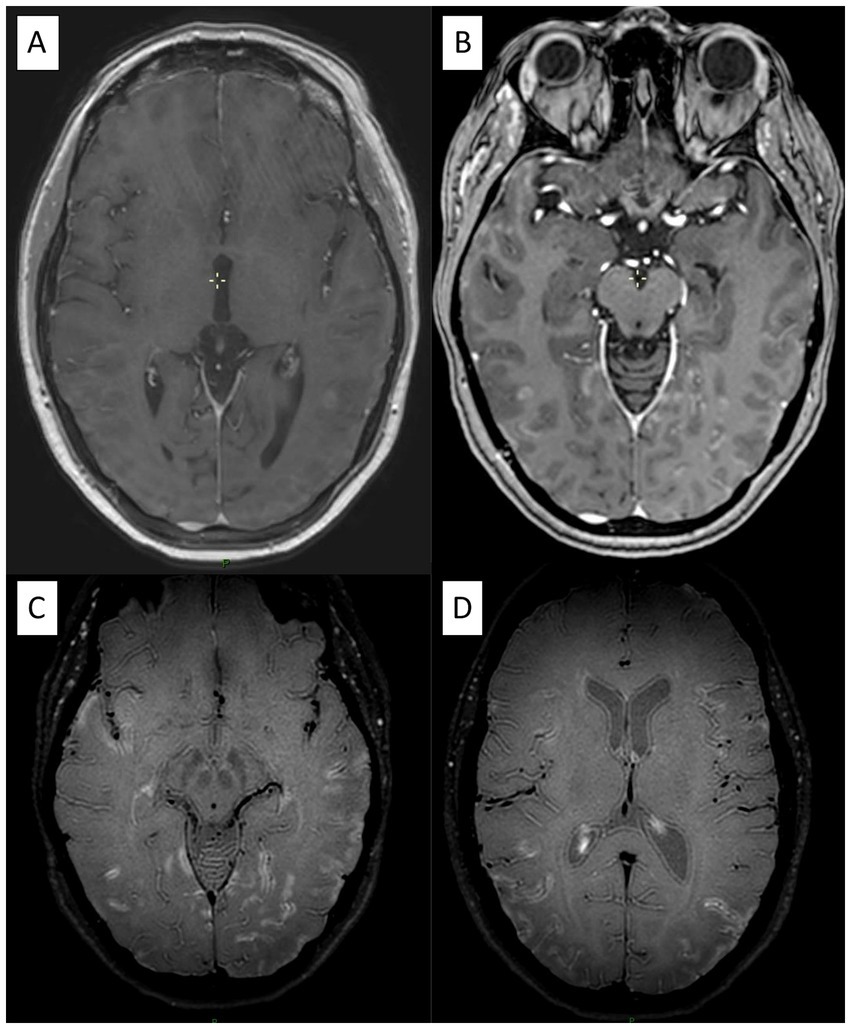

Figure 3. A 40-year-old patient with biopsy-proven small vessel vasculitis. (A) Post-gadolinium 3D T1-weighted MRI shows parenchymal enhancement in the parietal lobe and associated leptomeningeal enhancement (B). (C and D) VWI demonstrates diffuse and extensive leptomeningeal contrast enhancement.

VWI showed wall enhancement of the main and smaller trunks of the circle of Willis (Figure 4), with segmental vascular irregularities visualized on TOF in 4 PACNS patients and 2 SACNS (p = 0.37) Further details and biopsy correlation (when available) are provided in the Supplementary Table 2. For PACNS, VWI positive findings were reported in one case of small, one case of mediumand two cases of a combination of small and medium-vessel vasculitis. Interestingly, in one patient with PACNS there was a negative biopsy with positive VWI imaging and another patient had negative VWI imaging but positive biopsy (small-vessel involvement and lymphocytic pattern) (Supplementary Table 2). For SACNS, 2 patients presented with positive findings (large-vessel vasculitis) and 2 patients presented with negative findings (one small-vessel and one large-vessel vasculitis), but no brain biopsies were available.

The main parameters of interest in VWI are concentric wall thickening and vessel-wall enhancement (VWE) (24). Concentric wall thickening, although highly prevalent in patients with PACNS, can also be observed in reversible constriction syndrome (RCVS) and other pathologies (45). VWE is not specific for PACNS, as it has been detected in normal vessel segments of PACNS patients (46), other pathologies (24) and even in healthy controls (47). Additionally, the rate of arterial stenosis co-localizing with VWE varies (22, 45, 48). Despite promising results, the use of VWI remains limited and debated. The lack of standardized protocols, hardware differences, and variable timing with respect to diagnosis or treatment have hindered its broader adoption. Further studies are needed to clarify its accuracy across vessel sizes and histological patterns in PACNS. In our cohort, both PACNS and SACNS, we found negative results in case of small-vessel angiitis and positive findings in case of medium/large-vessel angiitis. In particular, within our cohort of PACNS, one patient had a positive VWI and negative biopsy (likely due to medium-size vessel involvement, that was not sampled) while another patient had a negative case of VWI and a positive biopsy (Figure 3), presumably reflecting very small-vessel involvement below the resolution of MRI. This confirms an inverse relationship between the size of the vessel involved and VWE, consistent with previous findings (22, 49), which demonstrate less frequent abnormalities in small-vessel angiitis or biopsy-diagnosed cases.